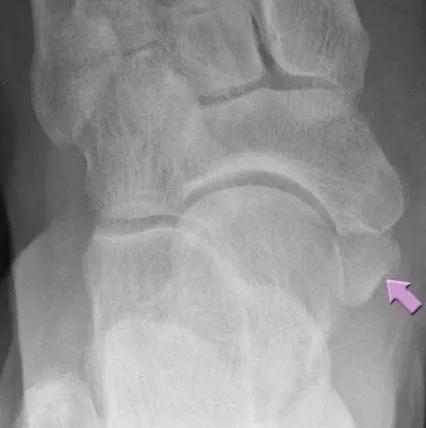

跗骨联合(骨桥):跗骨联合指的是两块或者两块以上跗骨之间出现了不该有的连接,对它们之间的活动造成限制,过去俗称为“骨桥”。学龄期,足部的骨骼逐渐成形,跗骨联合的部位也因为骨化变得僵硬起来,从而产生疼痛、经常扭伤、容易疲劳等表现。

跟舟骨桥